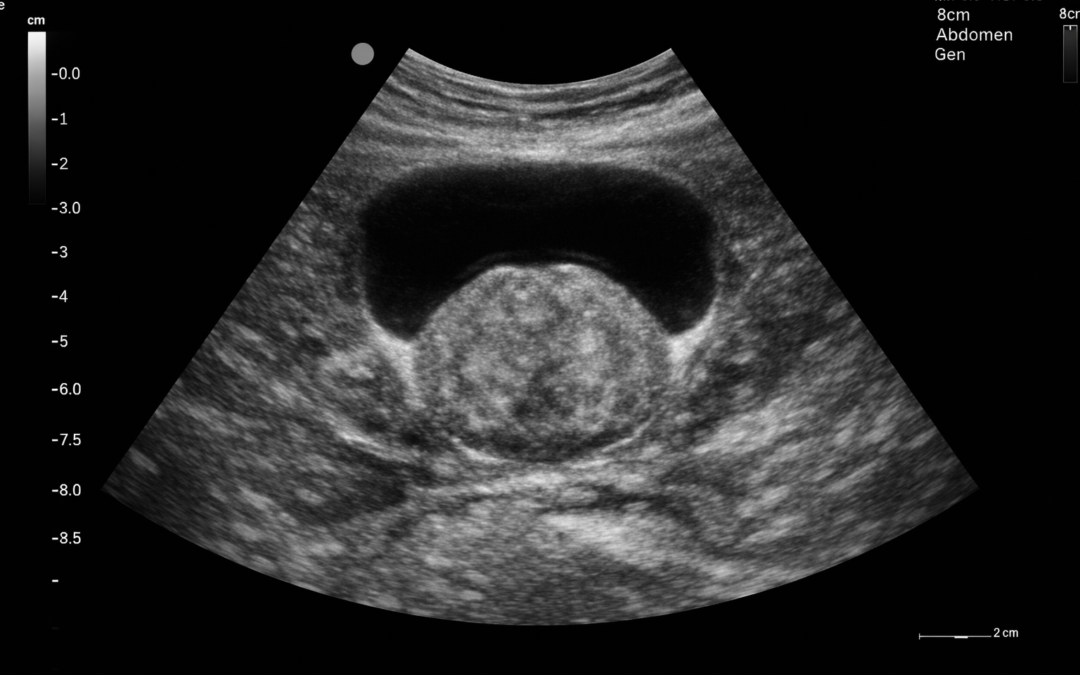

USG prostaty to badanie ultrasonograficzne gruczołu krokowego, czyli stercza. Prostata znajduje się pod pęcherzem moczowym i otacza początkowy odcinek cewki moczowej, dlatego jej powiększenie lub inne nieprawidłowości mogą wpływać na oddawanie moczu. USG pozwala ocenić przede wszystkim wielkość gruczołu krokowego, jego zarys i wybrane cechy anatomiczne.

Najczęściej wykonywane jest USG przezbrzuszne, podczas którego głowica aparatu przykładana jest do skóry podbrzusza. W takiej formie badania zwykle ważne jest odpowiednie wypełnienie pęcherza moczowego, ponieważ ułatwia to ocenę prostaty i okolicznych struktur.

W niektórych przypadkach wykonuje się USG przezodbytnicze, czyli badanie z użyciem specjalnej sondy wprowadzanej do odbytnicy. Taka metoda pozwala uzyskać dokładniejszy obraz prostaty. Mayo Clinic opisuje badanie transrektalne jako ultrasonografię, w której obraz prostaty uzyskuje się po umieszczeniu specjalnego przetwornika w odbytnicy.